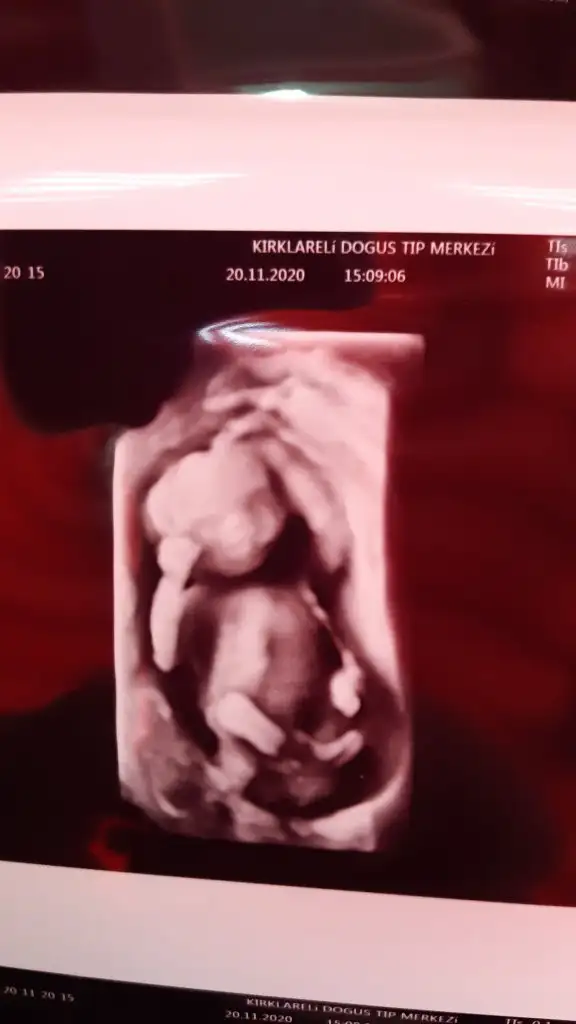

Allah bağışlasın18 haftalık olduk biz de artık cinsiyetimiz kesinleşti bir oğlum vardı bir erkek daha geliyorBugün de nifty testimin sonucu cıktı şükür bir risk saptanmamış Eki Görüntüle 2724286